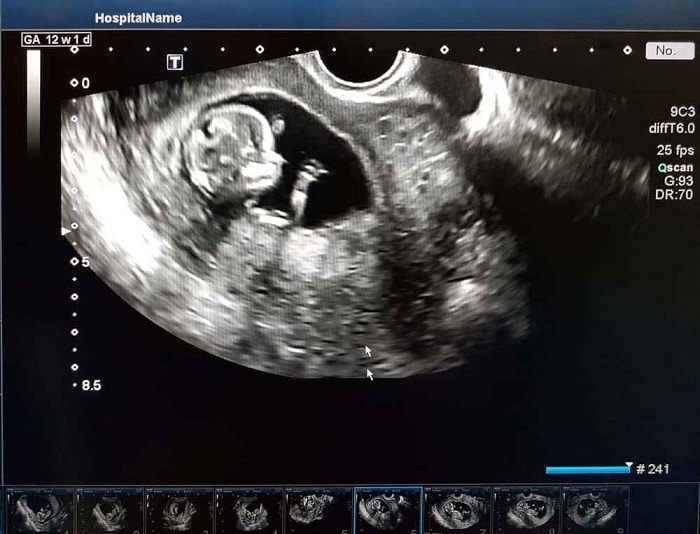

Setelah mendapat berita gembira melalui ujian kehamilan yang menunjukkan dua jalur, kegembiraan melimpah ruah, seringkali ingin dikongsi dengan orang ramai, termasuk dengan memuat naik gambar ultrasound di media sosial dengan kapsyen penuh syukur.

Namun, perlu diingat bahawa perkongsian tersebut sebenarnya tidak disyorkan.

Gambar imbasan perut mempunyai makna tersirat dalam Bahasa Arab. Untuk penjelasan lanjut, terdapat perkongsian daripada Pejabat Mufti Wilayah Persekutuan yang perlu kita fahami agar kita lebih peka terhadap perkara yang tidak patut dilakukan semasa mengandung.

Salam. Selalunya wanita yang mengandung akan scan perut mereka untuk tengok keadaan bayi dikandung.

Apakah hukum share gambar scan perut tersebut di media sosial?

Kami berpendapat hal demikian tidak elok dilakukan kerana bertentangan dengan asal maksud janin itu sendiri.

Janin itu berasal daripada perkataan Bahasa Arab yang membawa maksud ‘perkara yang tersembunyi.’ Justeru, tidak patut ditunjuk-tunjuk kepada orang melainkan ada keperluan seperti urusan perubatan dan pengajaran.

Dikhuatiri akan mengundang fitnah seperti aib dan sangkaan-sangkaan manusia.

Walau bagaimanapun, gambar foto bukanlah seperti aurat fizikal yang haram dilihat secara langsung, melainkan membawa kepada syahwat dan fitnah.

Begitu juga organ dalaman manusia seperti hati, jantung dan rahim bukanlah dalam kategori aurat kerana demikian bukanlah makna perhiasan berdasarkan penjelasan Rasulullah SAW dan para sahabat.